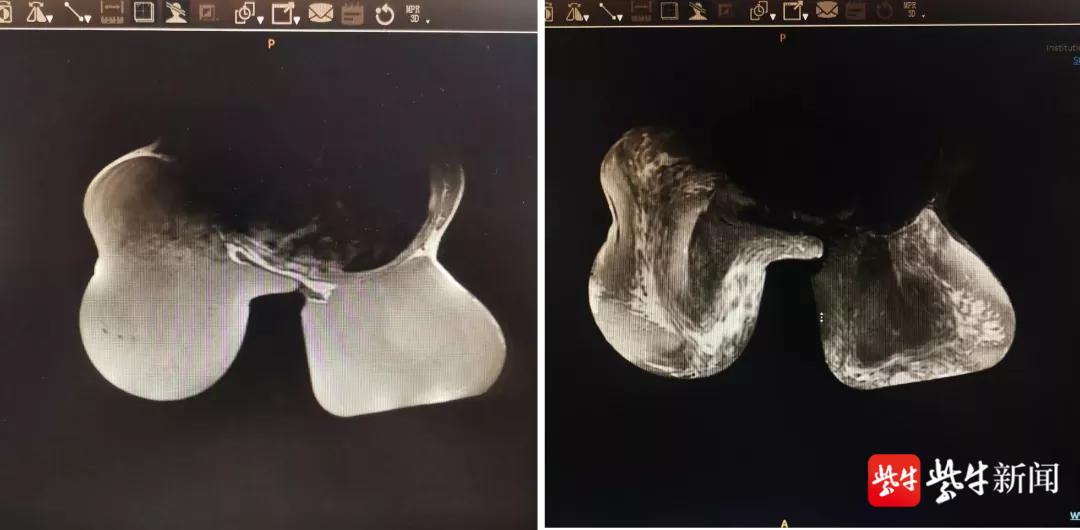

根据患者乳房磁共振和头颅磁共振等检查报告显示,首先排除了乳房肿瘤、脑垂体、肾上腺疾病的可能。由于青少年进入青春发育期后,体内激素分泌将会达到相对较高的水平,位于人体丘脑下部的脑垂体控制着体内激素的分泌,经过系统全面的检查后发现,患者诗琪的各项激素水平均处于正常范围。排除众多可能病因、综合其临床病史及检查结果,最后,考虑该患者属于乳腺作为受体对雌激素过度敏感,以致于在青少年发育期乳腺过度发育引起的“巨乳症”。

患者影像检查资料